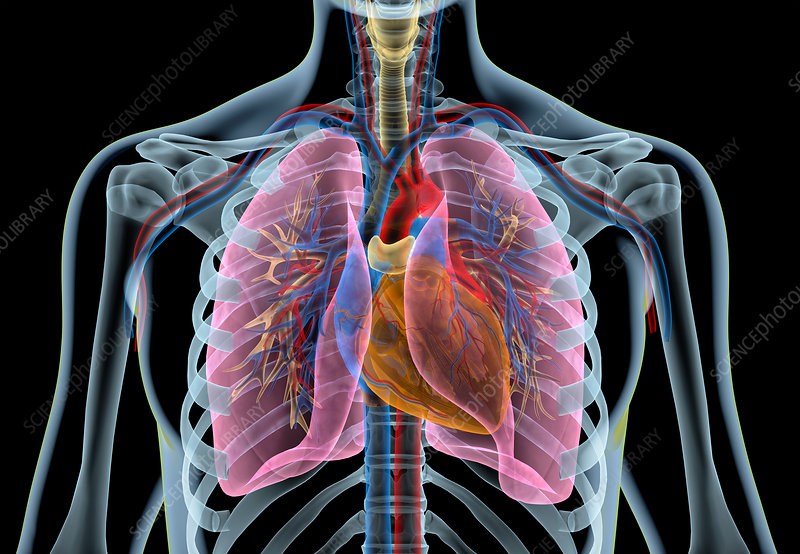

This Medical Imaging Science Discipline Course is a continuation of the MRI Series in which the students develop their radiographic techniques in radiation imaging examinations. The students are introduced to chest, abdomen, head and spine radiography. Radiation Safety Practice and Image Quality Factors are further learnt in enhancing the student's competencies towards conventional radiography.

Medical Radiation Imaging II is a second year course under the Bachelor of Medical Imaging Science program and it introduces the undergraduates to imaging sciences in radiography, specifically the imaging principles, techniques and skills, and radiation protection involved in radiographic procedures and examinations of the axial region of the human anatomy. It is a continuation from MRI I and it covers Chest, Abdomen, Spine and Skull Radiography. Furthermore, it will also help the undergraduate to develop and enhance their written and oral communication (English). The course is significant as it establishes vital connections that enable students to complete the year of study through team effort and correlating with other courses for clinical applications.